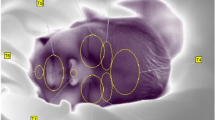

Thermal images of each neonate were captured every 15 s by IRT. First, a gradient image was created from the neonatal thermal image with a range of 4 °C at 0.2 °C intervals. The gradient image was based on the maximum temperature and each 0.2 °C interval is shown in the same color (Fig. 5a and b).

A representative example of a thermal image captured using IRT. (a) An IRT image of a neonate during the measurement. The IRT was placed on the ceiling of the incubator, which enabled visualization of the temperature distribution in the whole neonate body. (b) We created the gradient images at 0.2 °C intervals from a neonatal image using IRT and specified a target region of the thermal image visually.

Next, a periodic temperature change was seen in the whole body and synchronized in the whole abdomen so that we could capture the same heat cycle in any area chosen (Supplementary Figure S1). We chose an analysis area that was not affected by the ECG cable or a staff member’s hand. Therefore, the target area and its size differed among measurements. The analysis area ranged in size from around 1 to 4 cm2. Each analysis was performed on data in which images of only the neonate were continuous for more than 25 min (more than 100 images). We showed the number of pixels for each piece of analyzed data (Table 2). Finally, we calculated the average temperature in the target area and converted it into time-series data (Fig. 6). The following data exclusion criteria for the analysis were applied: (1) when the analysis range fluctuated for the thermal image; (2) when more than 25 min of continuous data could not be obtained due to frequent overlapping of obstacles such as staff member’s hands in the analysis range; and (3) when the neonate started to cry during the filming.